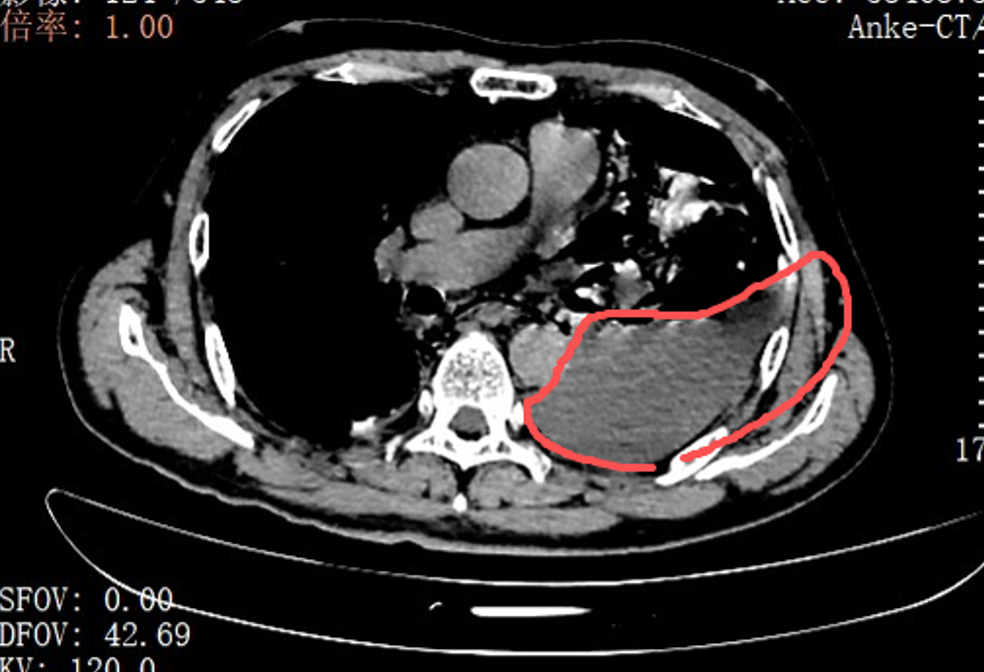

面对这一凶险急症,胸外科主任刘继先的手术团队当天就对张叔实施了胸腔镜下食道修补微创手术。打开胸腔的那一刻,在场的医护人员都愣住了:整个左侧胸腔里,全是叉烧包的菜叶子、食物残渣,混着脓液和消化液,到处都是。

红圈区域是食物残渣、消化液破入食管

手术团队拿着吸引器,一点点清理、冲洗,花了很长时间才将胸腔里的每一点食物残渣都清干净。随后,团队找到了食道下段那道长达10厘米的裂口,用可吸收线小心翼翼地完成了分层修补。